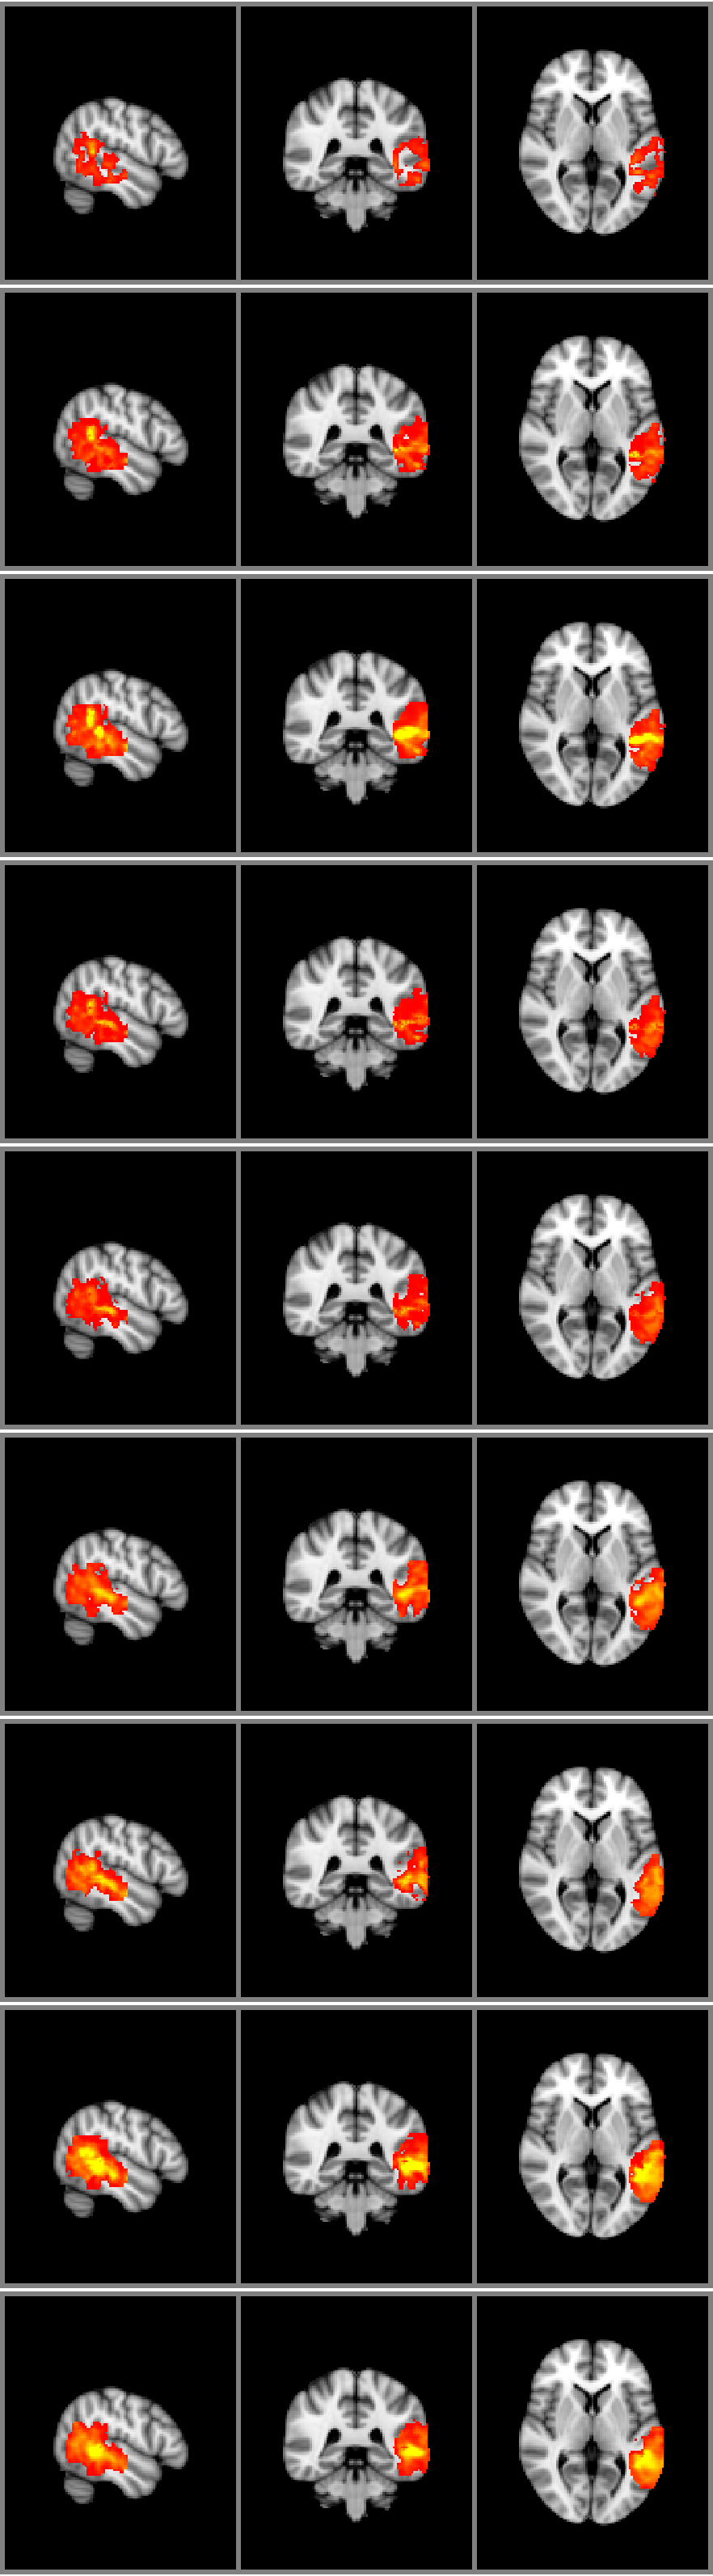

Refer to caption

Figure 3: A number of predicted AD activation profiles for different regions in the brain.

We first qualitatively inspected the predictions made by the GP and its ability to extract a continuous profile of AD image phenotypes. Figure 3 shows a set of example traces collected from various locations of the brain. The asterisks in the figure show the observed voxel-specific z-scores at their respective MMSE scores. Also shown are the predicted posterior mean activation profile and the predicted posterior variance of the activation profile. The profiles show varying degrees of variability depending on brain region the profile. Some profiles appear to show several peaks along the MMSE axis while others show a delayed and gradual increase at the higher end of the MMSE spectrum. Looking at the spatial distribution of predictions, Figure 4 shows the changes predicted activation in the temporal lobe with equidistant increases in MMSE scores, starting with MMSE value of 202020 at top and finishing with MMSE value of 303030 in the bottom row of the figure. Figure 4a shows the predicted mean activation while figure 4b shows the predicted variance in the activation. Clearly visible is the increase in activation spread and intensity. Also very clearly visible is an intermediate increase in variance at MMSE (444th and 555th image row). These images correspond to images at MMSE values that are not contained in the data set. Also, there is a tendency of the variance to decrease with increasing MMSE. This effect is primarily due to the increased quality of the images as patients become more similar to control subjects (MMSE=303030).

(a) The predictive mean

(b) The predictive variance

Figure 4: Changes in temporal lobe activation with improving MMSE. Left: Predicted mean activation; Right: Predicted activation variance.